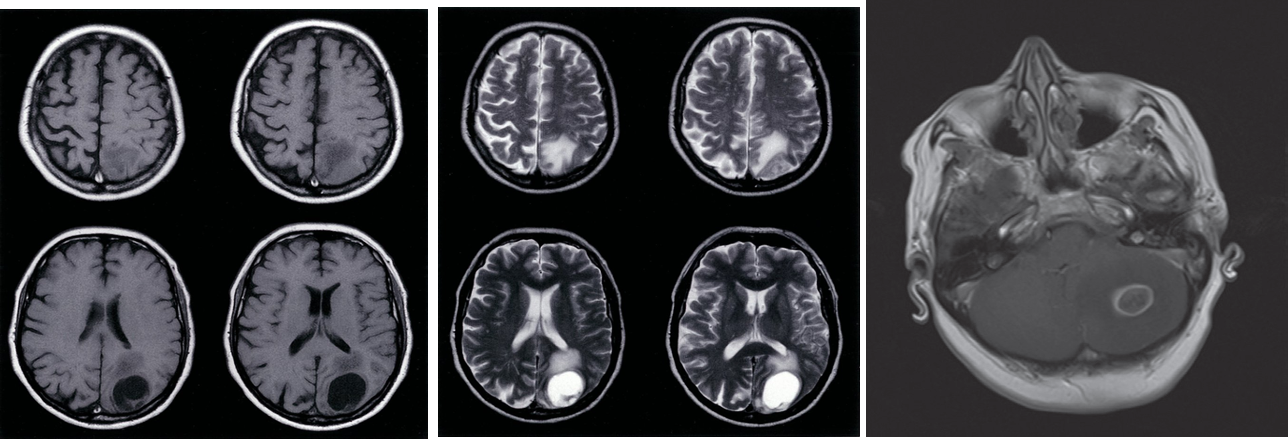

MRI head (T1 & T2-weighted; without contrast; axial plane) of a patient with lung carcinoma. A solitary, well-circumscribed, predominantly hypointense (T1) hyperintense (T2) mass in the left occipital lobe is accompanied by perifocal edema

Enhanced T1-weighted MRI scan showing a ring-enhancing cerebellar metastasis